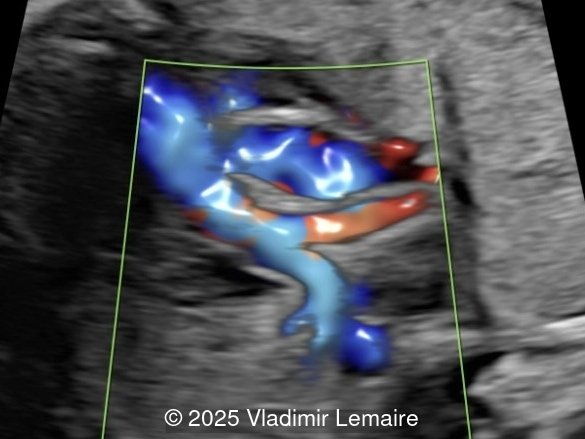

Our images demonstrate the following:

- Image 5: The right ventricular outflow tract view with color Doppler demonstrates a small main pulmonary artery when compared to the dilated aorta due to pulmonary stenosis.

- Image 6: The three-vessel-trachea view with color Doppler shows the discrepant size of the great arteries with the pulmonary artery smaller than the aorta. Note the presence of antegrade blood flow in both arteries.

Color Doppler confirms the presence of an overriding aorta with blood draining from both ventricles, through the ventricular septal defect into the aortic root. Due to high perfusion, inflow into the aorta appears aliased. At the level of the three-vessel-trachea view, color Doppler can also demonstrate a small pulmonary artery. Flow is antegrade across the ductus arteriosus in mild Tetralogy of Fallot and can be reversed in severe cases. Color Doppler can help differentiate various subgroups of TOF as postnatal ductal dependency of the pulmonary circulation can be associated with cyanosis of the newborn.